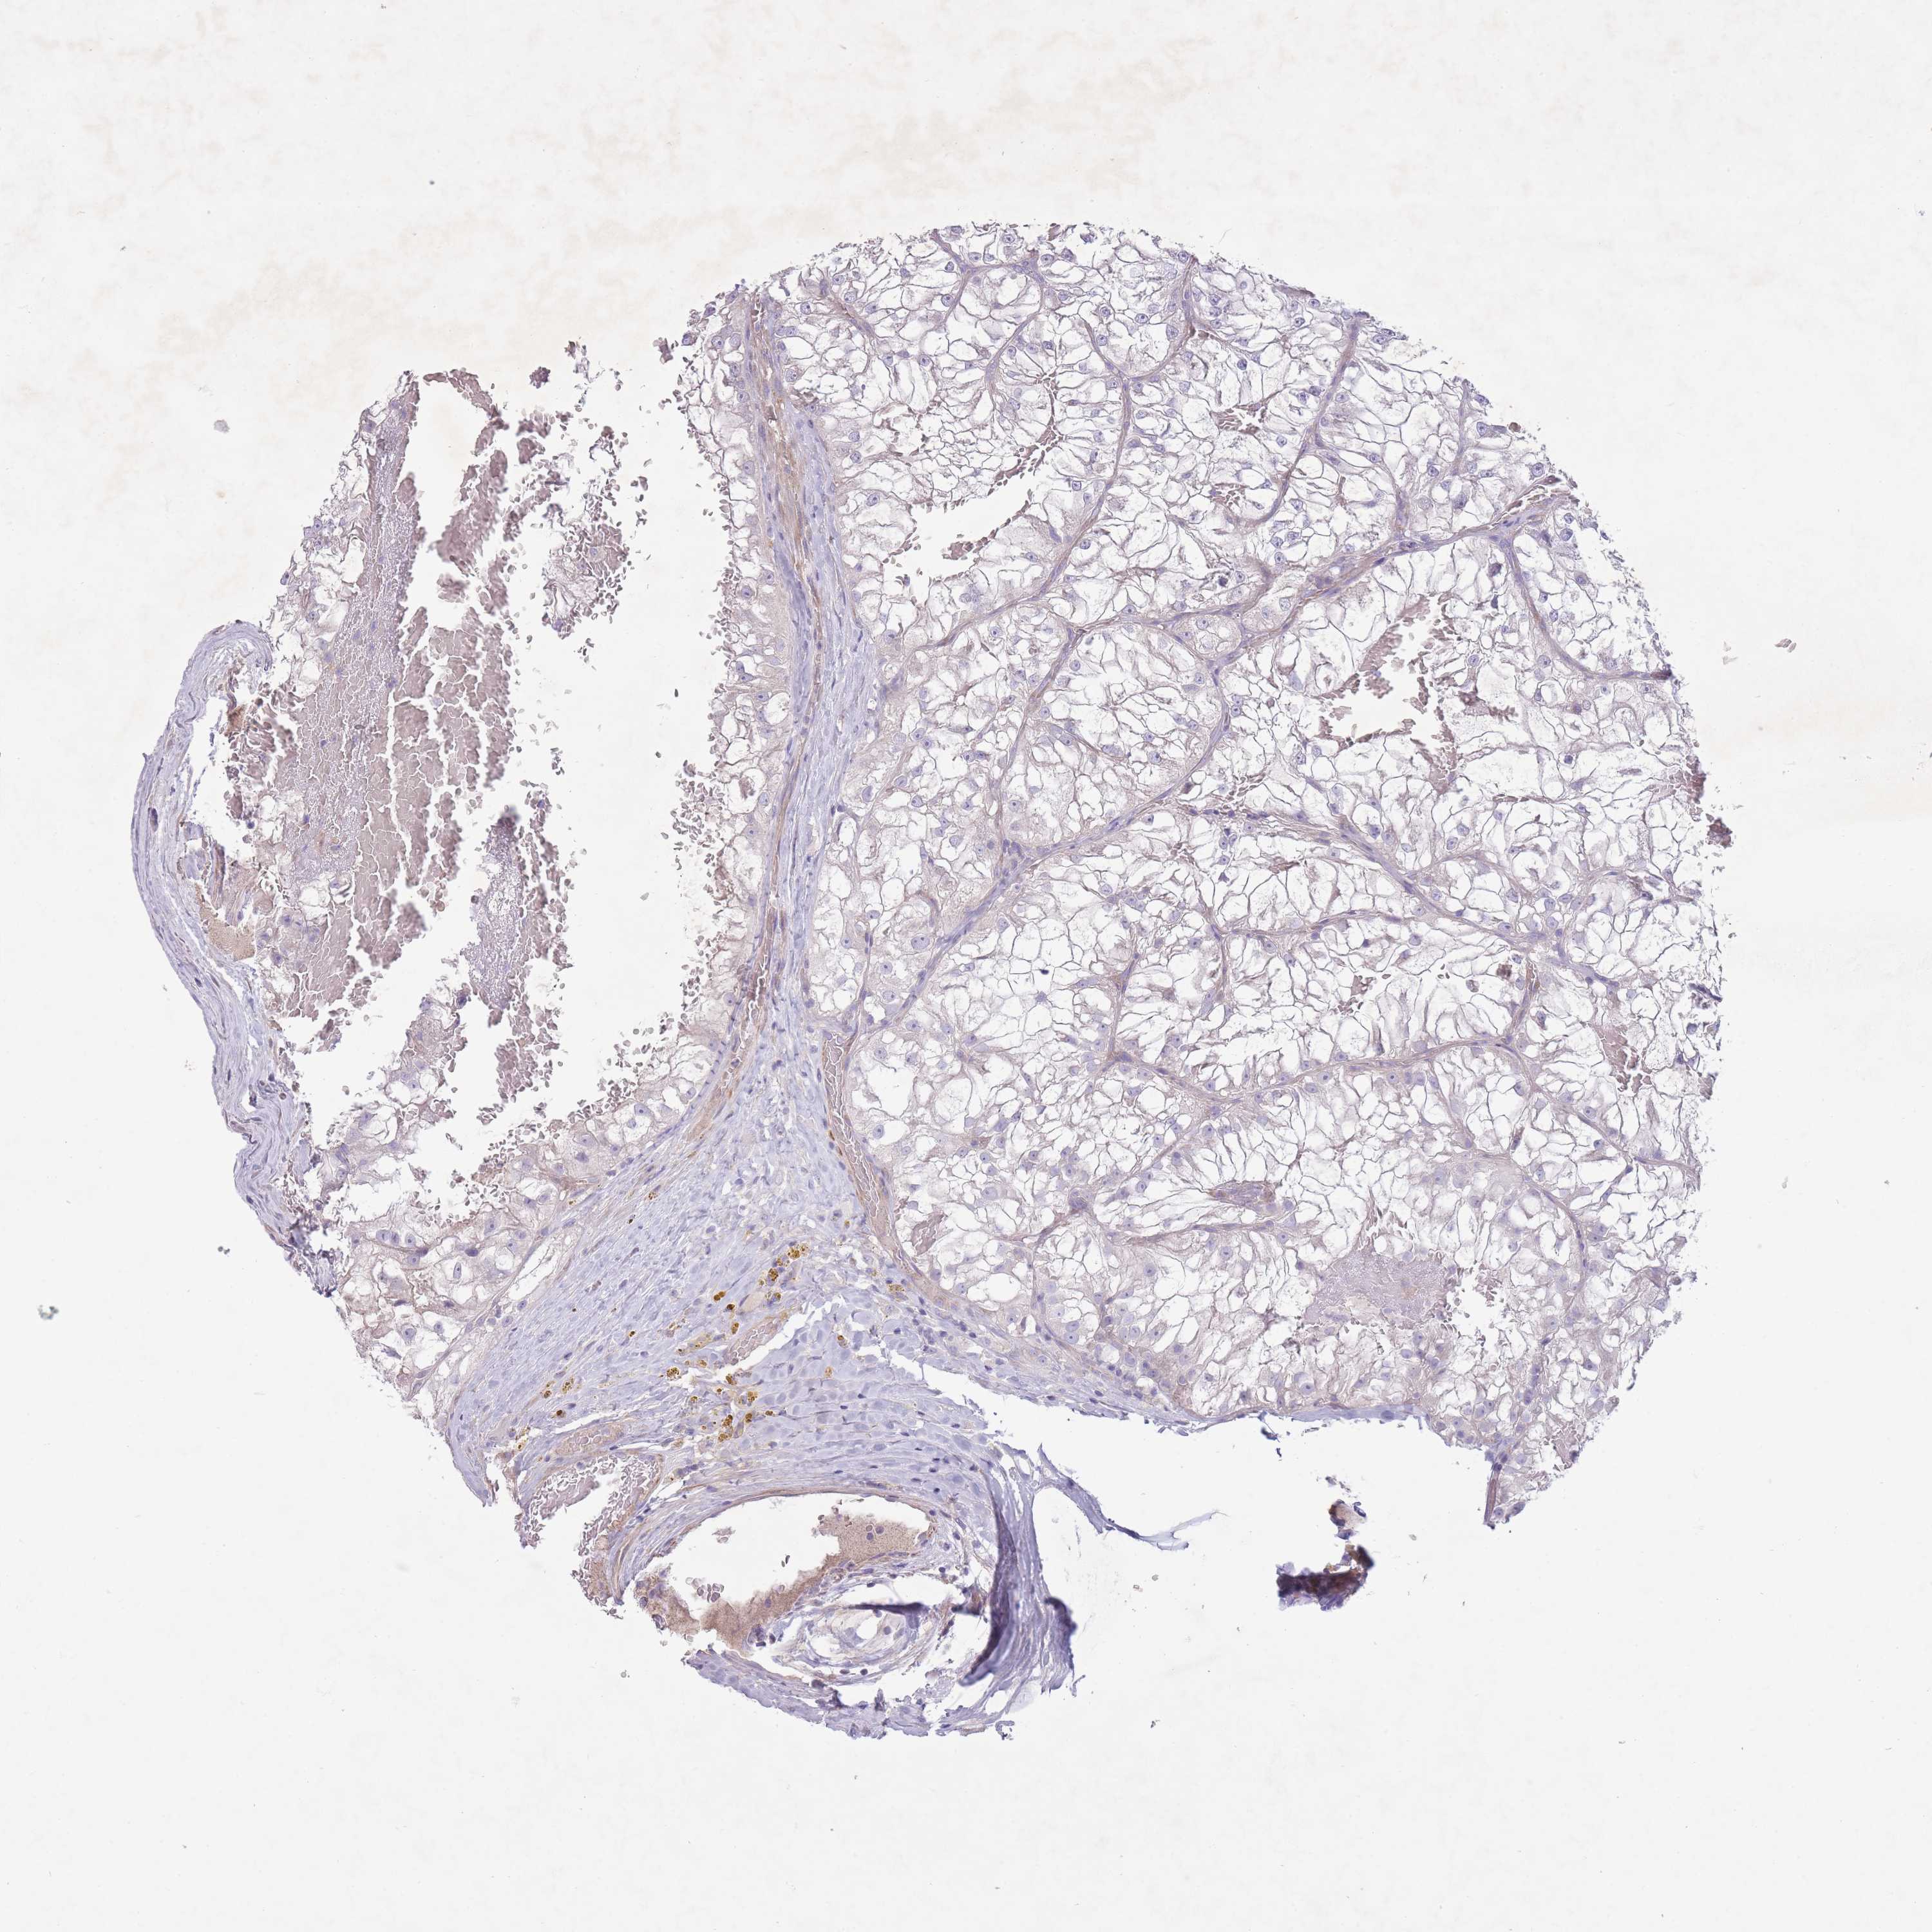

KIDNEY RENAL CLEAR CELL CARCINOMA (VALIDATION) - Interactive survival scatter ploti

The Survival Scatter plot shows the clinical status (i.e. dead or alive) for all individuals in the patient cohort, based on the same data that underlies the corresponding Kaplan-Meier plots. Patients that are alive at last time for follow-up are shown in blue and patients who have died during the study are shown in red.

The x-axis shows the expression levels (FPKM) of the investigated gene in the tumor tissue at the time of diagnosis. The y-axis shows the follow-up time after diagnosis (years). Both axes are complimented with kernel density curves demonstrating the data density over the axes. The top density plot shows the expression levels (FPKM) distribution among dead (red) and alive patients (blue). The right density plot shows the data density of the survived years of dead patients with high and low expression levels respectively, stratified using the cutoff indicated by the vertical dashed line through the Survival Scatter plot. This cutoff is automatically defined based on the FPKM cutoff that minimizes the p-score. The cutoff can be changed by dragging the vertical line or by entering a cutoff value in the square labeled "Current cut-off".

Under the Survival Scatter plot the p-score landscape (black curve; left axis) is shown together with dead median separation (red curve; right axis). Dead median separation is the difference in median mRNA expression between patients who have died with high and low expression, respectively. It is calculated as follows: median FPKM expression of dead patients with high expression - median FPKM expression of dead patients with low expression. This is intended to aid the user in visually exploring custom cutoffs and the associated p-scores and dead median separation.

Individual patient data is displayed and can be filtered by clicking on one or more of the category buttons on the top of the page. Categories describing expression level and patient information include: high, low, alive, dead, female, male and tumor stages. The scale of the x-axis can be toggled between linear and log-scale by clicking on the "x log" button. Mouse-over function shows TCGA ID, patient information and mRNA expression (FPKM) for each patient.

& Survival analysisi

Kaplan-Meier plots summarize results from analysis of correlation between mRNA expression level and patient survival. Patients were divided based on level of expression into one of the two groups "low" (under cut off) or "high" (over cut off). X-axis shows time for survival (years) and y-axis shows the probability of survival, where 1.0 corresponds to 100 percent.

PNPLA5 is not prognostic in Kidney Renal Clear Cell Carcinoma (validation)